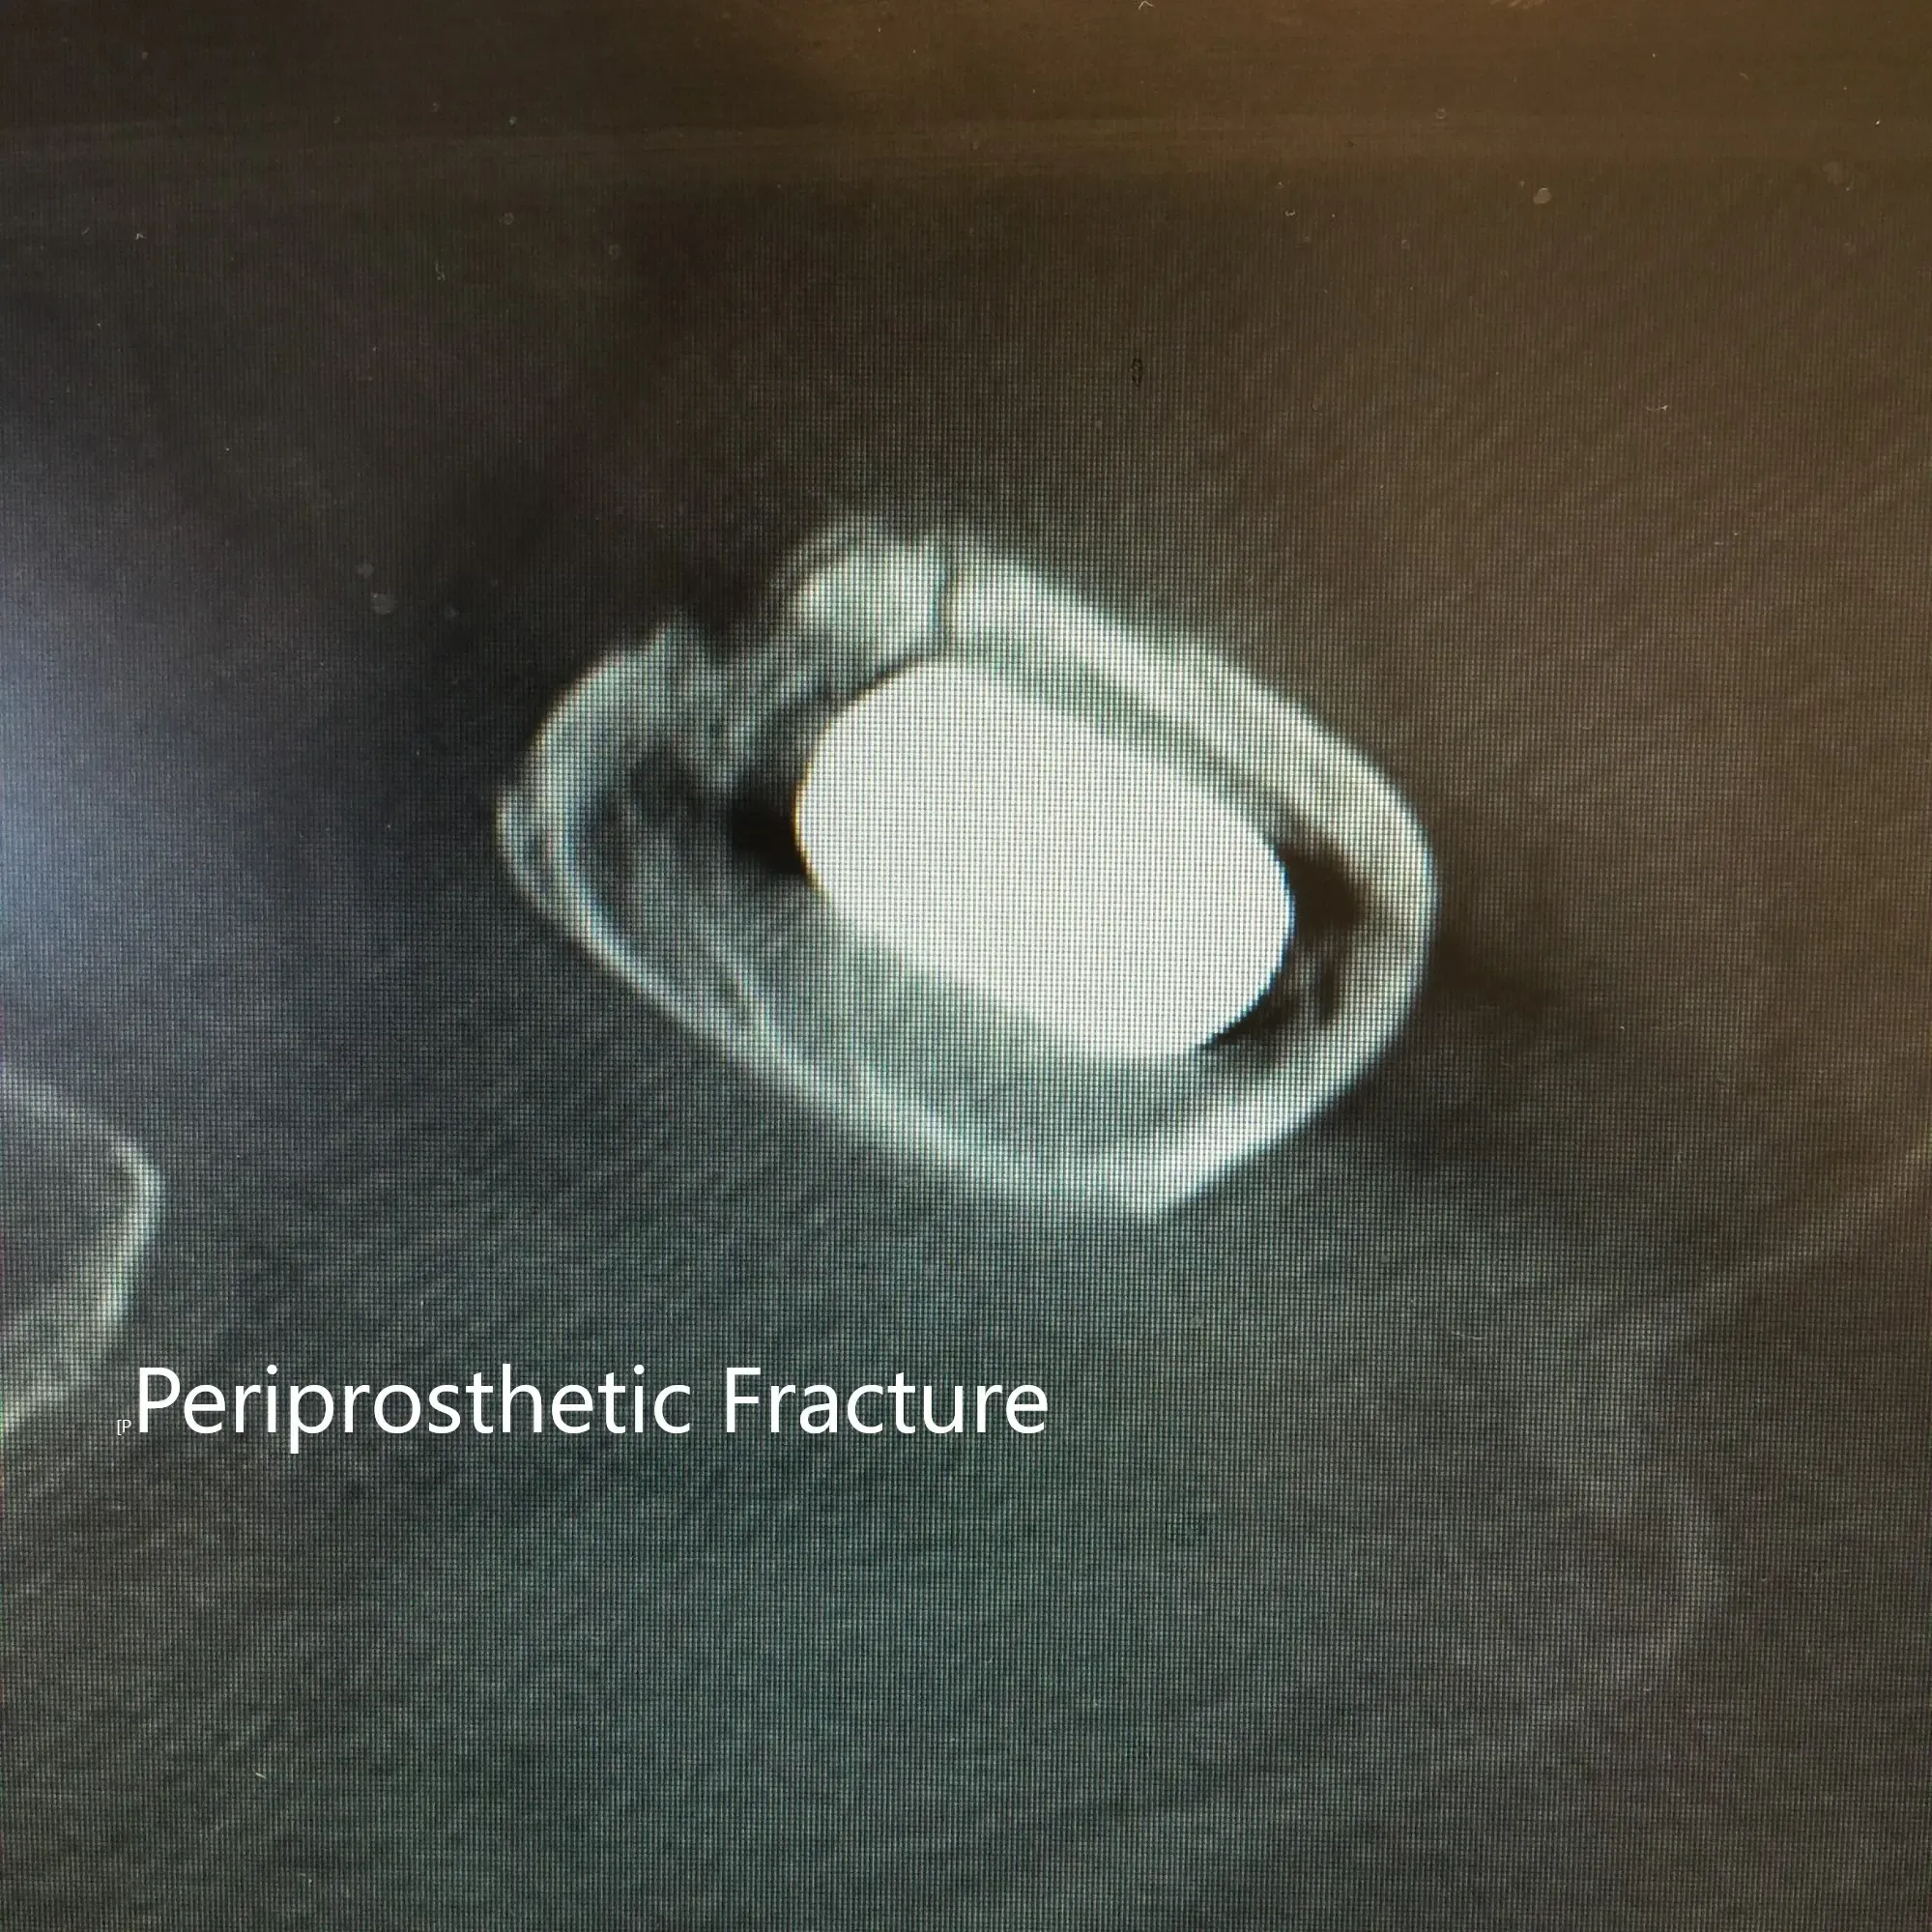

La tomografía computarizada y la radiografía de la cadera izquierda revelaron una fractura periprotésica no desplazada del fémur proximal anteromedialmente con subsidencia del tallo.